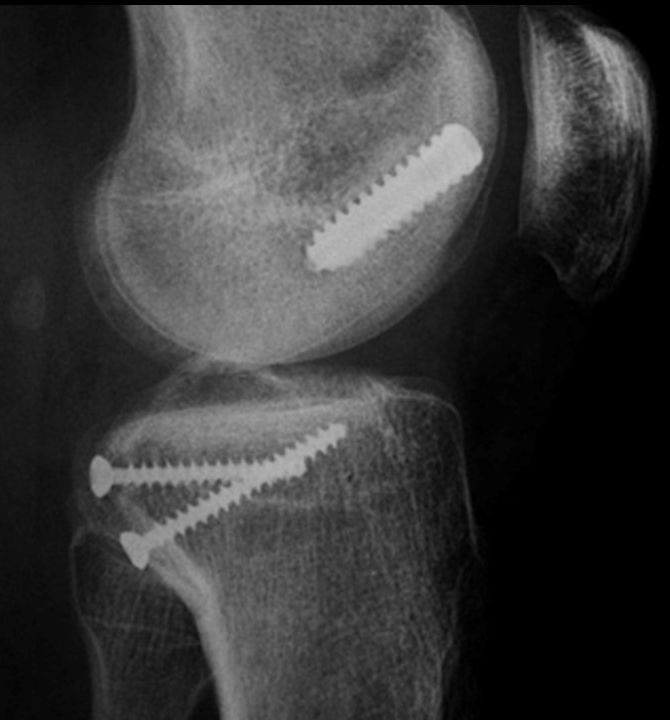

After clinical examination normal x-rays of the knee ap and lateral view is performed. In chronic posterior knee instability, we add standing long film ap x-rays bilateral as well as lateral long film (1/3 Femur and 2/3 Tibia) to detect hyperextension and to measure the slope (Fig 1).

Fig 1 - X- RAY: Long Standing Film  for Alignement Evaluation  and Lateral Hyperextension for Slope Evaluation

This is followed by stress x-rays routinely. In contrast to Telos used stress x-rays we prefer the kneeling view according to Bartlett which does not allow muscular compensation of the instability (Fig 2). MRI is also performed routinely to get information about the personality of PCL rupture and associated lesions.

Fig 2 - Bartlett Stress View bilateral